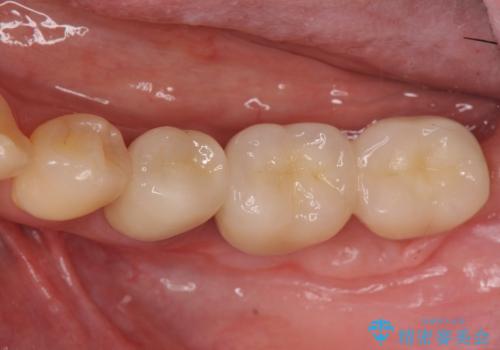

遊離歯肉移植術を併用した、破折歯のインプラント治療

- 83.6万円(インプラント×2・アバットメント×2・クラウン×2)費用は治療当時の料金となります

インプラント周囲の角化歯肉が存在することにより、歯ブラシがしやすくなりインプラントにトラブルが起きる確率を減らしより長期的な予後を望むことができます。